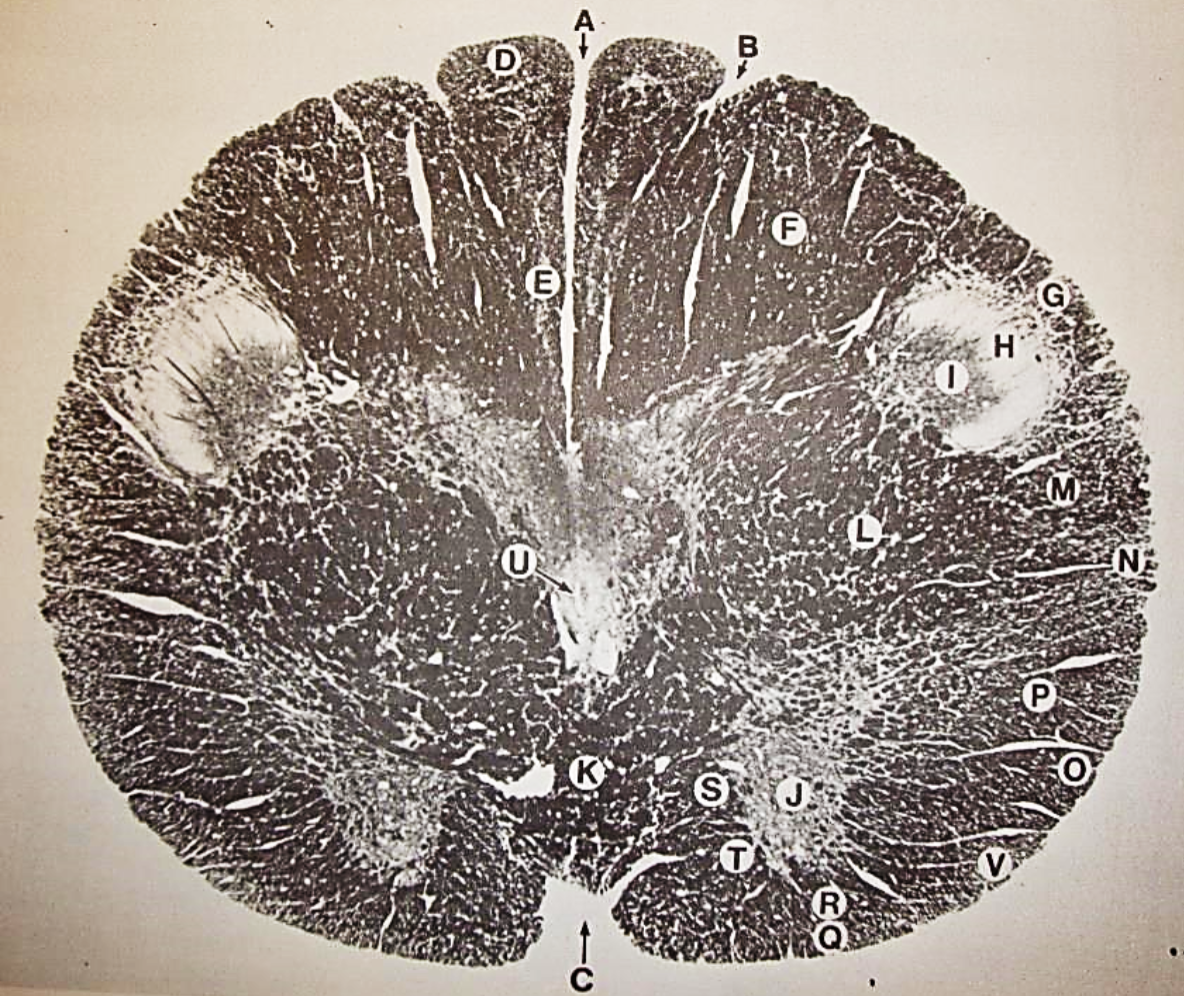

A

fasciculus gracilis

B

gracile nucleus

C

fasciculus cuneatus

D

cuneate nucleus

F

internal arcuate fibers

G

decussation of internal arcuate fibers

H

medial lemniscus

I

hypoglossal nucleus

J

dorsal motor nucleus vagus

K

solitary fasciculus

L

solitary nucleus

M

dorsal longitudinal fasciculus

N

spinal trigeminal tract

O

spinal trigeminal nucleus

P

posterior spinocerebellar tract

Q

anterior spinocerebellar tract

R

spinal lemniscus

S

lateral vestibulospinal tract

T

rubrospinal tract

U

lateral reticular nucleus

V

medial accessary olivary nucleus

W

pyramidal (corticospinal) tract

X

arcuate nucelus

Y

medial longitudinal fasciculus

Z

tectospinal tract

a

fascicles of hypoglossal nerve